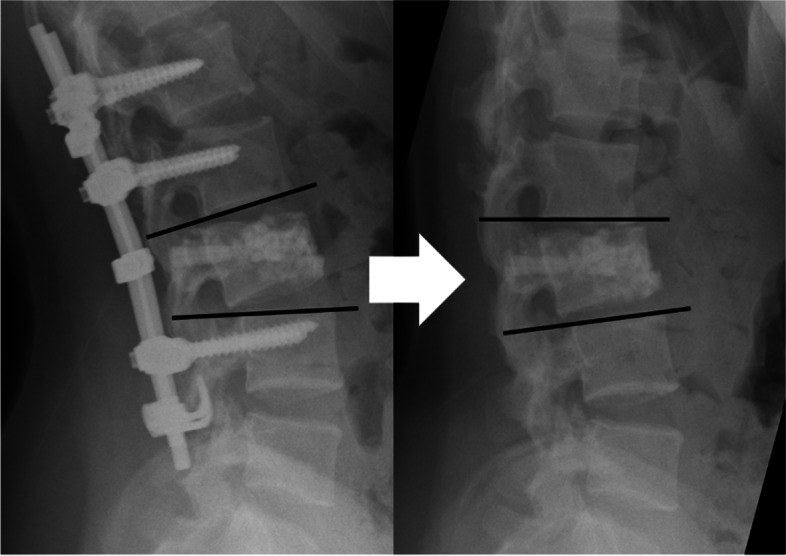

Final kyphotic deformity was defined as a kyphotic angle greater than 25° at the final observation, based on a previous study in which patients with kyphosis greater than 25° had poor clinical outcomes [13]. Loss of correction was defined as an increase in the kyphotic angle greater than 15° at the final observation compared with kyphotic angle after posterior fixation (Fig. 4).

Fig. 4.

Loss of correction